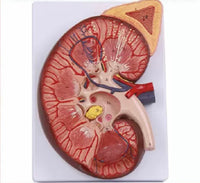

Modelo de Riñón maxizado con Glándula renal rinon

Modelo de Riñón maxizado con Glándula renal riñón

sistema urinario maximizado

Medidas del producto: 21 x 28 x 9 cm